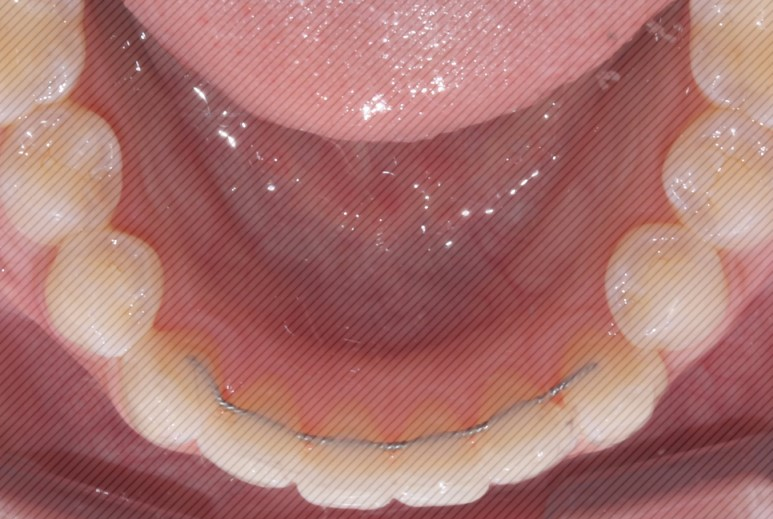

2D교정 교정기간 : 4개월

상악 오른쪽 앞니의 부분 돌출도

이상없이 고르게 교정이

완료 되었습니다.

하악 크라우딩

(자리가 없어 덧난 경우) 도

예쁘게 제자리를 찾아 갔습니다.

4개월만에 개선된 모습을 보니

환자분도 굉장히 만족해하셨는데요.

대신 그만큼 유지장치도

잘 착용해주시고

관리도 잘 해주셔야 한다는 점!

잊지 마세요 :)